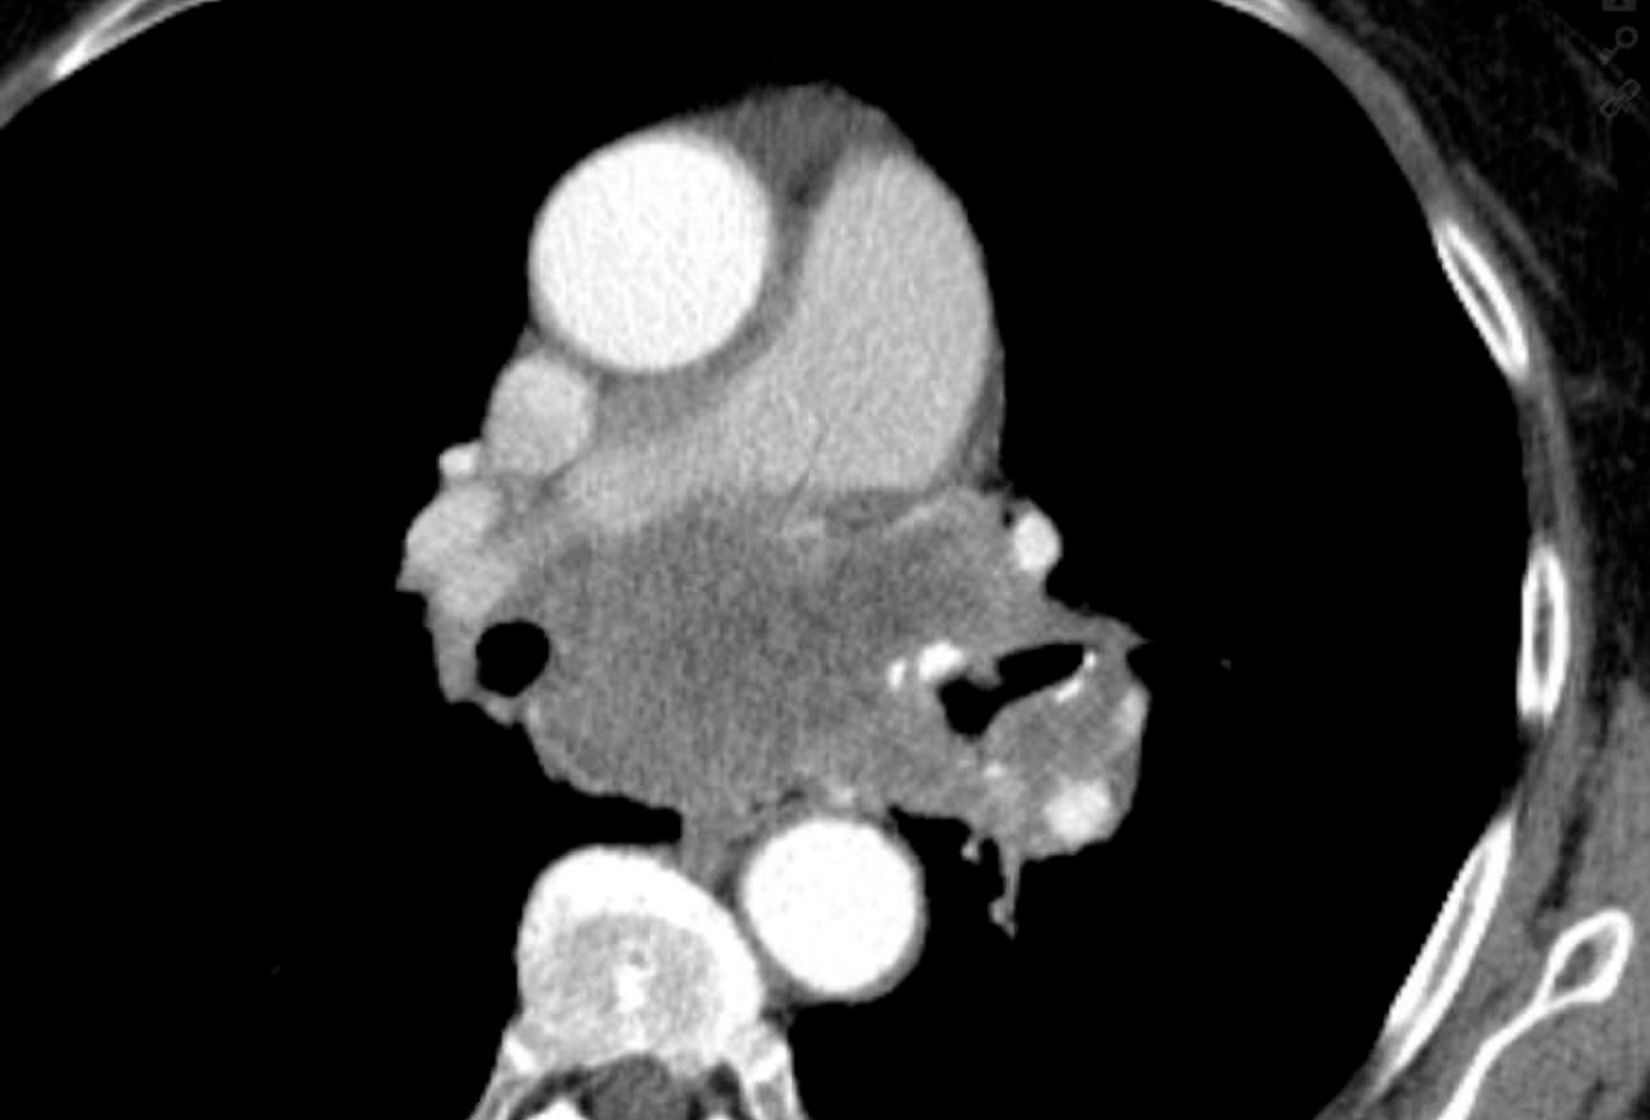

Neben dem Ultraschall und dem konventionellen Röntgen wird vielfach für das weitere therapeutische Vorgehen die Schnittbilddiagnostik eingesetzt. Dazu gehören die Computertomographie (CT) und die Magnetresonanztomographie (MRT). Bei diesen Untersuchungen werden bestimmte Bereiche des Körpers so untersucht, dass auch kleinste Gewebeveränderungen genau dargestellt werden.

An beiden Standorten, der DIAKO und dem Malteser Krankenhaus, können CT-Untersuchungen durchgeführt werden. Des Weiteren gibt es die Möglichkeit in der DIAKO bestimmte Patientengruppen auch mittels sog. Low-Dose-(Niedrig-Dosis-)-CT-Protokollen zu untersuchen.